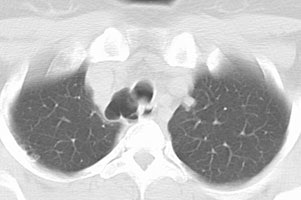

Tracheal diverticulum: The patient shown below was being evaluated for active pulmonary tuberculosis and was incidentally discovered to have a tracheal diverticulum. Note the slightly irregular wall of the diverticulum which can be seen in almost one-third of cases. Click here to view cine image which nicely confirms communication with the trachea. |